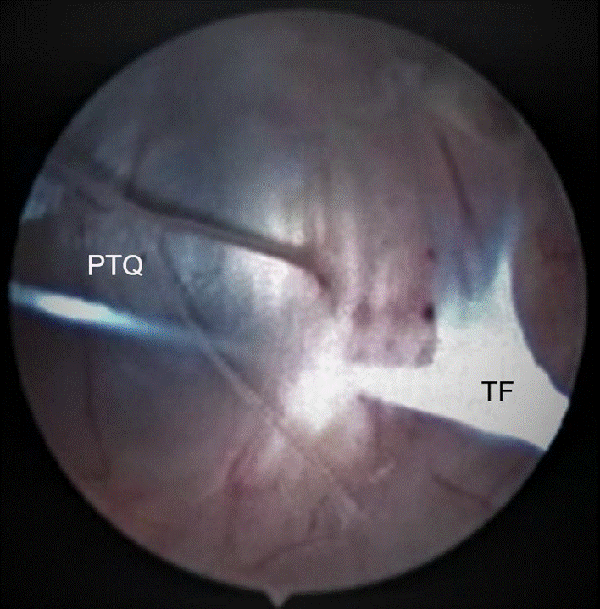

En los casos de quistes paraventriculares, se abordó directamente al mismo, se navegó en su interior buscando el área translúcida o aquella donde la pared ventricular genera una prominencia, y se realizó la fenestración de manera similar a la explicada para los quistes intraventriculares (Figura 4).

Figura 4: Imagen endoscópica de un abordaje cistoventricular. Al navegar dentro de la cavidad quística se observa la presencia de múltiples tabiques fibrosos (TF), es necesario reconocer la pared translúcida del quiste (PTQ) la cual constituye el área en donde se realiza la ostomía.